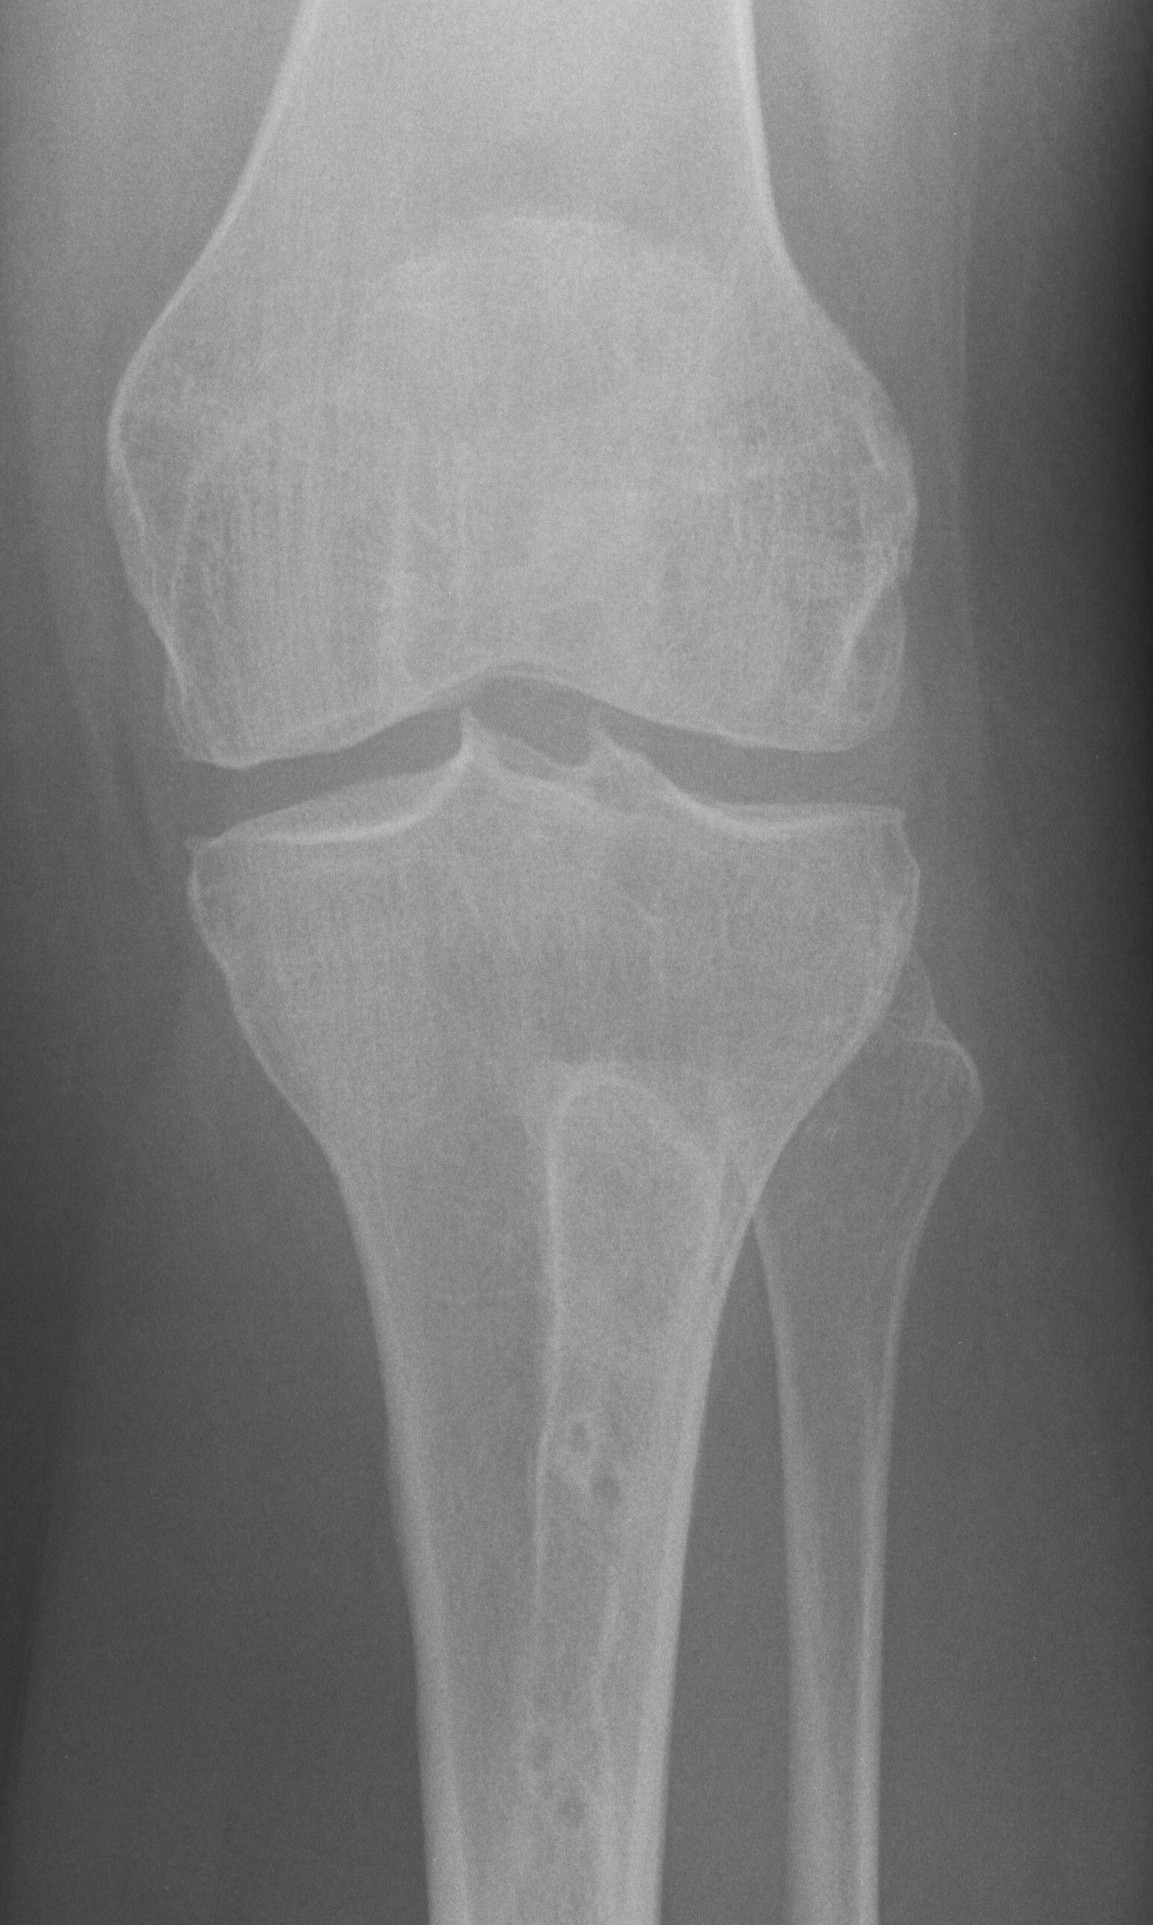

X-ray

Narrowing / osteophytes / sclerosis

Tilt / subluxation